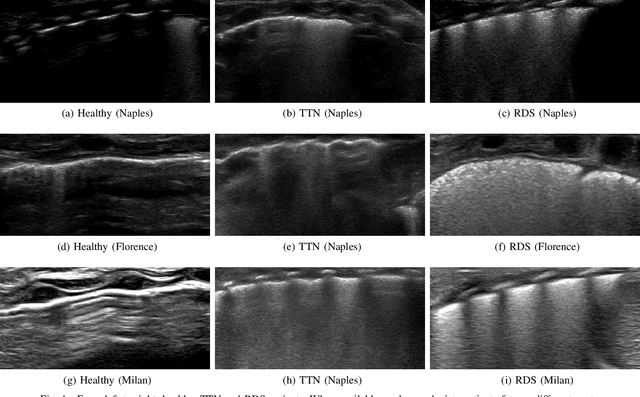

Abstract:Lung ultrasound imaging is reaching growing interest from the scientific community. On one side, thanks to its harmlessness and high descriptive power, this kind of diagnostic imaging has been largely adopted in sensitive applications, like the diagnosis and follow-up of preterm newborns in neonatal intensive care units. On the other side, state-of-the-art image analysis and pattern recognition approaches have recently proven their ability to fully exploit the rich information contained in these data, making them attractive for the research community. In this work, we present a thorough analysis of recent deep learning networks and training strategies carried out on a vast and challenging multicenter dataset comprising 87 patients with different diseases and gestational ages. These approaches are employed to assess the lung respiratory status from ultrasound images and are evaluated against a reference marker. The conducted analysis sheds some light on this problem by showing the critical points that can mislead the training procedure and proposes some adaptations to the specific data and task. The achieved results sensibly outperform those obtained by a previous work, which is based on textural features, and narrow the gap with the visual score predicted by the human experts.